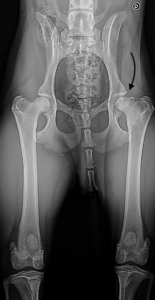

Résumé : Zyon est un jeune chiot croisé Bodeguero de 10 mois qui

présente une boiterie du postérieur droit

Cette boiterie est en évolution depuis 1,5 mois, en renforcement malgré plusieurs traitements anti- inflammatoires. La radiographie du bassin objective une morphologie anormale de la tête du fémur droit Il s’agit à la base d’une pathologie vasculaire du col et de la tête du fémur en croissance qui va évoluer vers une déformation ostéo- cartilagineuse, une fissuration et / ou déformation du cartilage articulaire et de la douleur.

Cette pathologie est aussi dénommée « nécrose aseptique de tête fémorale »